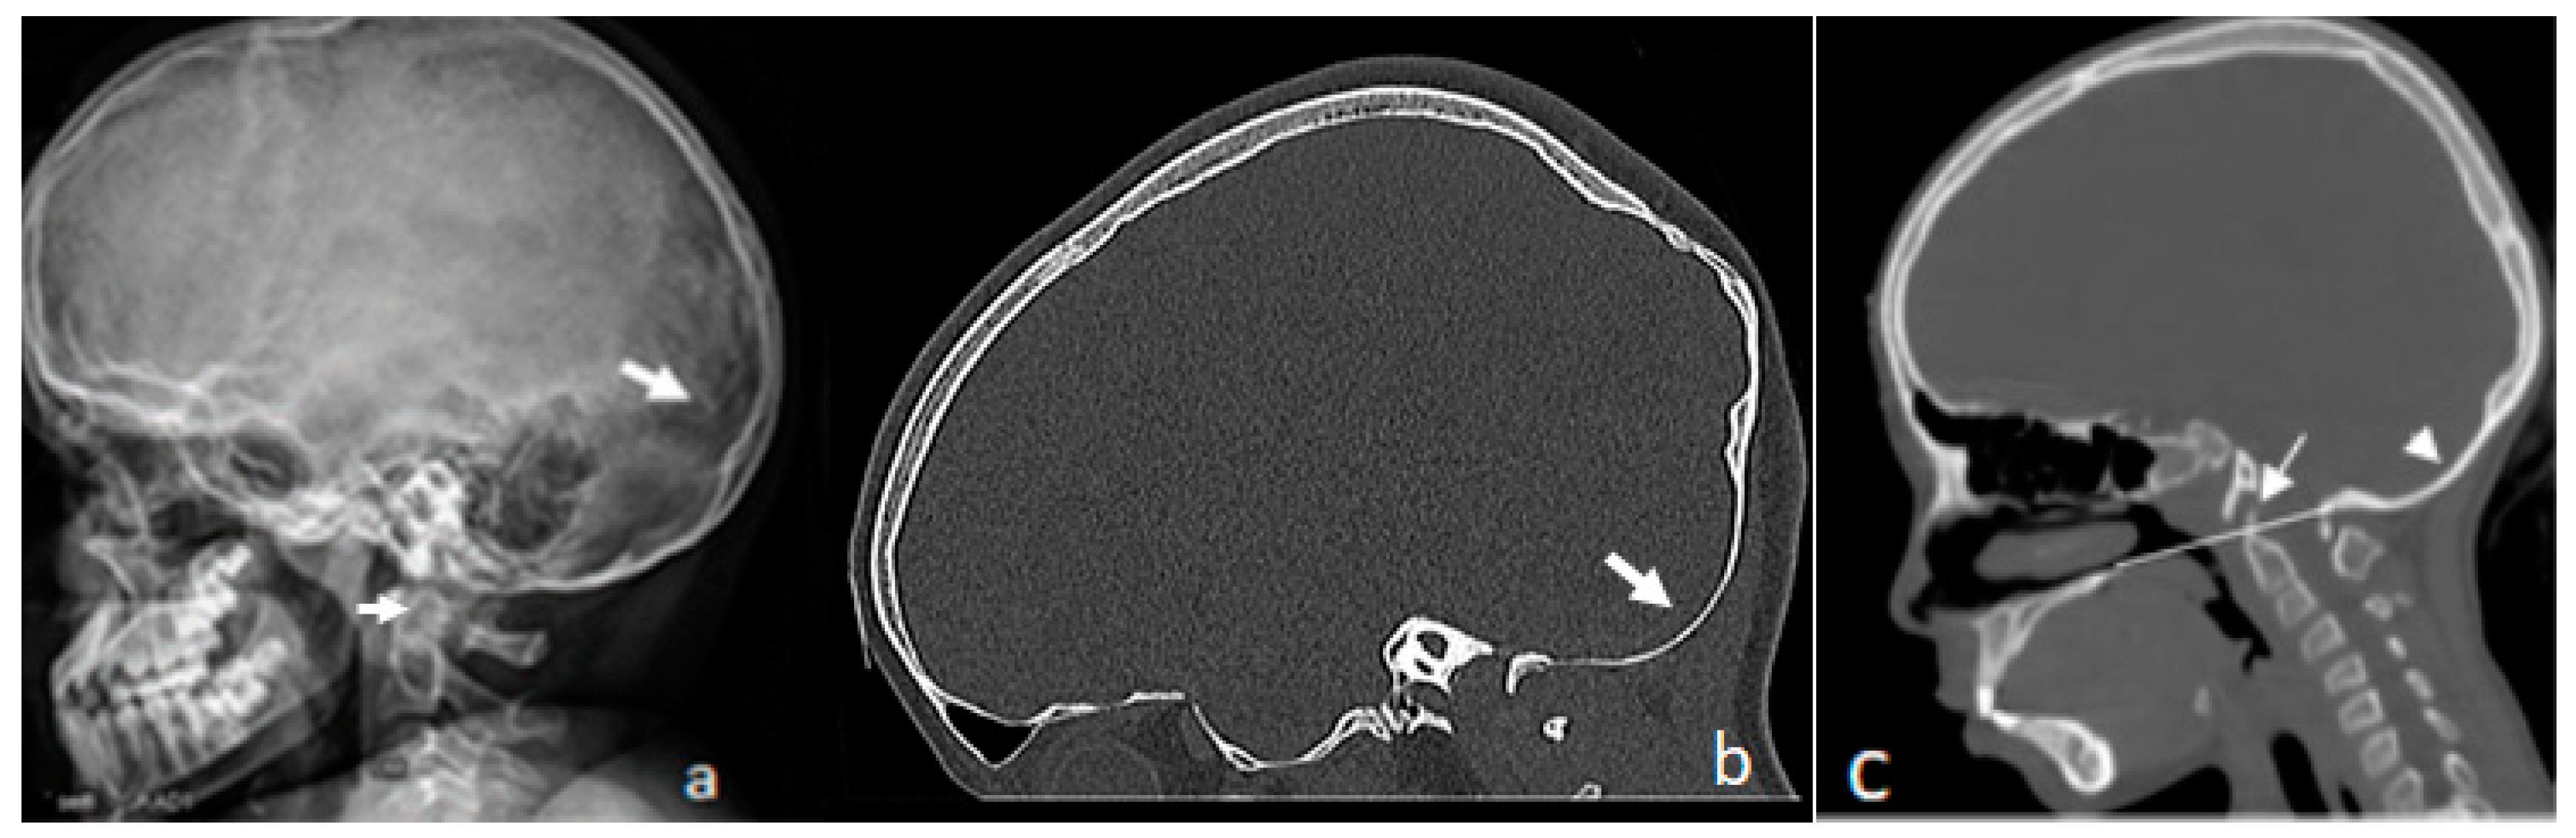

3.1. Patients with Osteogenesis Imperfecta Type I

Patients with Osteogenesis Imperfecta Type IVB